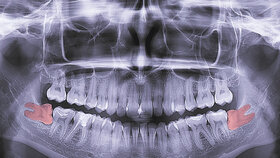

In der Metaanalyse der US-Forschungsgruppe wurden 15 Studien berücksichtigt. So ergab sich eine Gesamtheit von 1.366 Frauen mit und 2.919 Frauen ohne die Einnahme oraler Kontrazeptiva. Alveoläre Ostitis – auch Alveolitis sicca genannt – ist bei normalen Zahnextraktionen selten. Bei Weisheitszahnentfernungen tritt sie allerdings häufig auf: Es werden Prävalenzen von bis zu 30 Prozent angegeben [Daly et al., 2022].

In der vorliegenden Studie konnte gezeigt werden, dass sich das Risiko für eine alveoläre Ostitis bei Weisheitszahn-Extraktionen unter der Einnahme der Pille verdoppelte – dies auch nach Berücksichtigung von Antibiotika- und Analgetika-Gabe. Studien, in denen es um Extraktionen anderer Zähne ging, wurden nicht einbezogen.